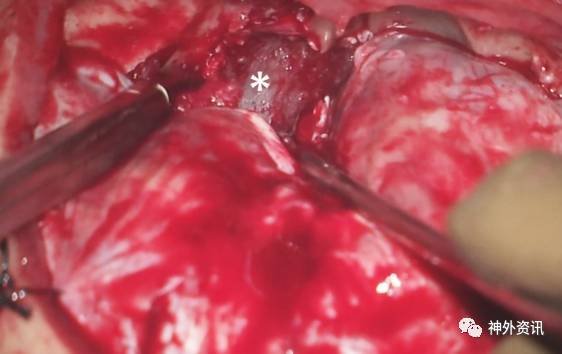

图10. 利用吸引器对额叶实现动态牵拉。将嗅球进行锐性分离,暴露硬膜外扩展的肿瘤前部(星形)。术中图像展示的是一侵犯鼻腔的前颅底软骨肉瘤切除术(上文图1)。锐性分离嗅球直接造成硬膜敞开并且显露肿瘤的硬膜内部分。